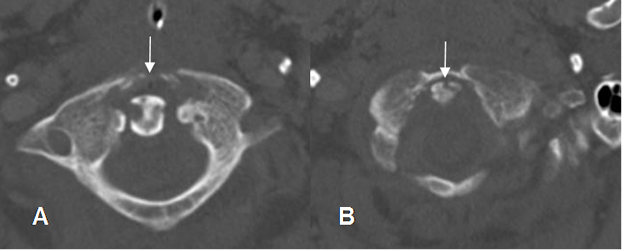

Fig 30 A. Osteomielitis aguda.

A: Rx lateral y B: TAC axial. Herida por arma de fuego, con proyectil localizado hacia el lado izquierdo del arco anterior de C1.

Fig 30 B. Osteomielitis aguda.

A y B: TAC axial. Igual paciente anterior. La bala ocasiona lesiones en el arco de C1 y la odontoides.